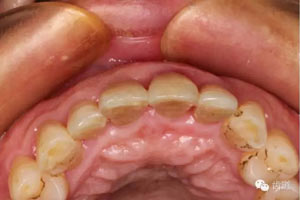

初診照片(合面照)

臨床檢查:11,21伸長(zhǎng)1-2mm,松動(dòng)1度,叩(+),21齦緣稍紅腫,唇側(cè)牙槽骨較豐滿,前牙咬合早接觸,中低位笑線,口腔衛(wèi)生一般。